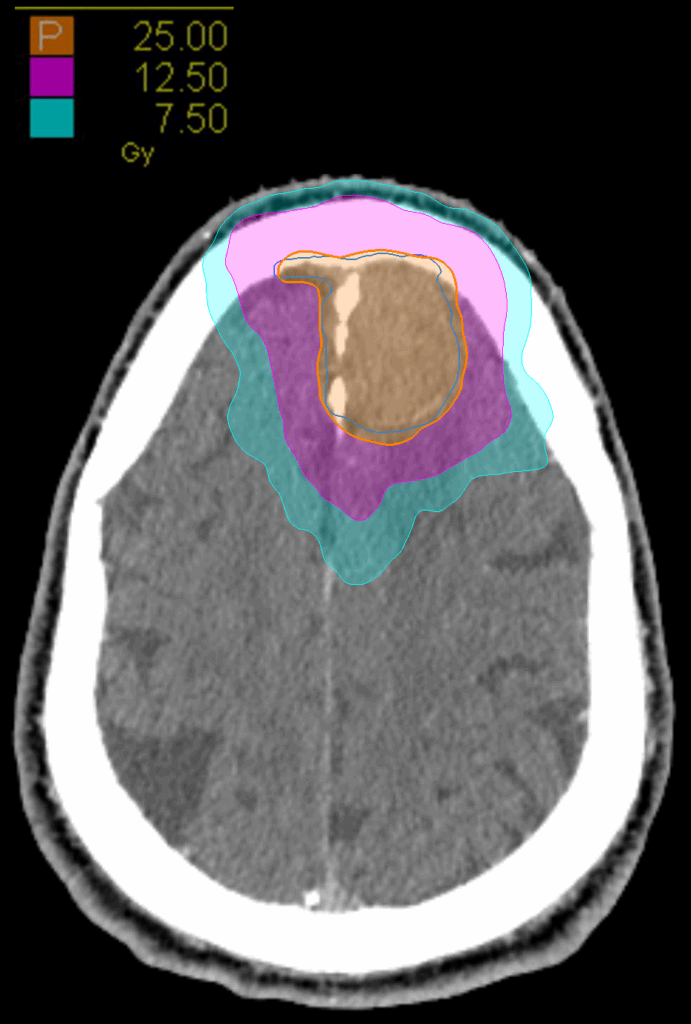

Treatment Plan Images

Fractionation

25 Gy in 5 fractions

PTV(s) Volume

PTV, 27.6 cc

Dose Distributions

- Prescription to the 83.2% isodose line

- Max. dose 30.1 Gy

New Conformality Index (nCI)

nCi = 1.24

Gradient Index (GI)

GI = 3.88